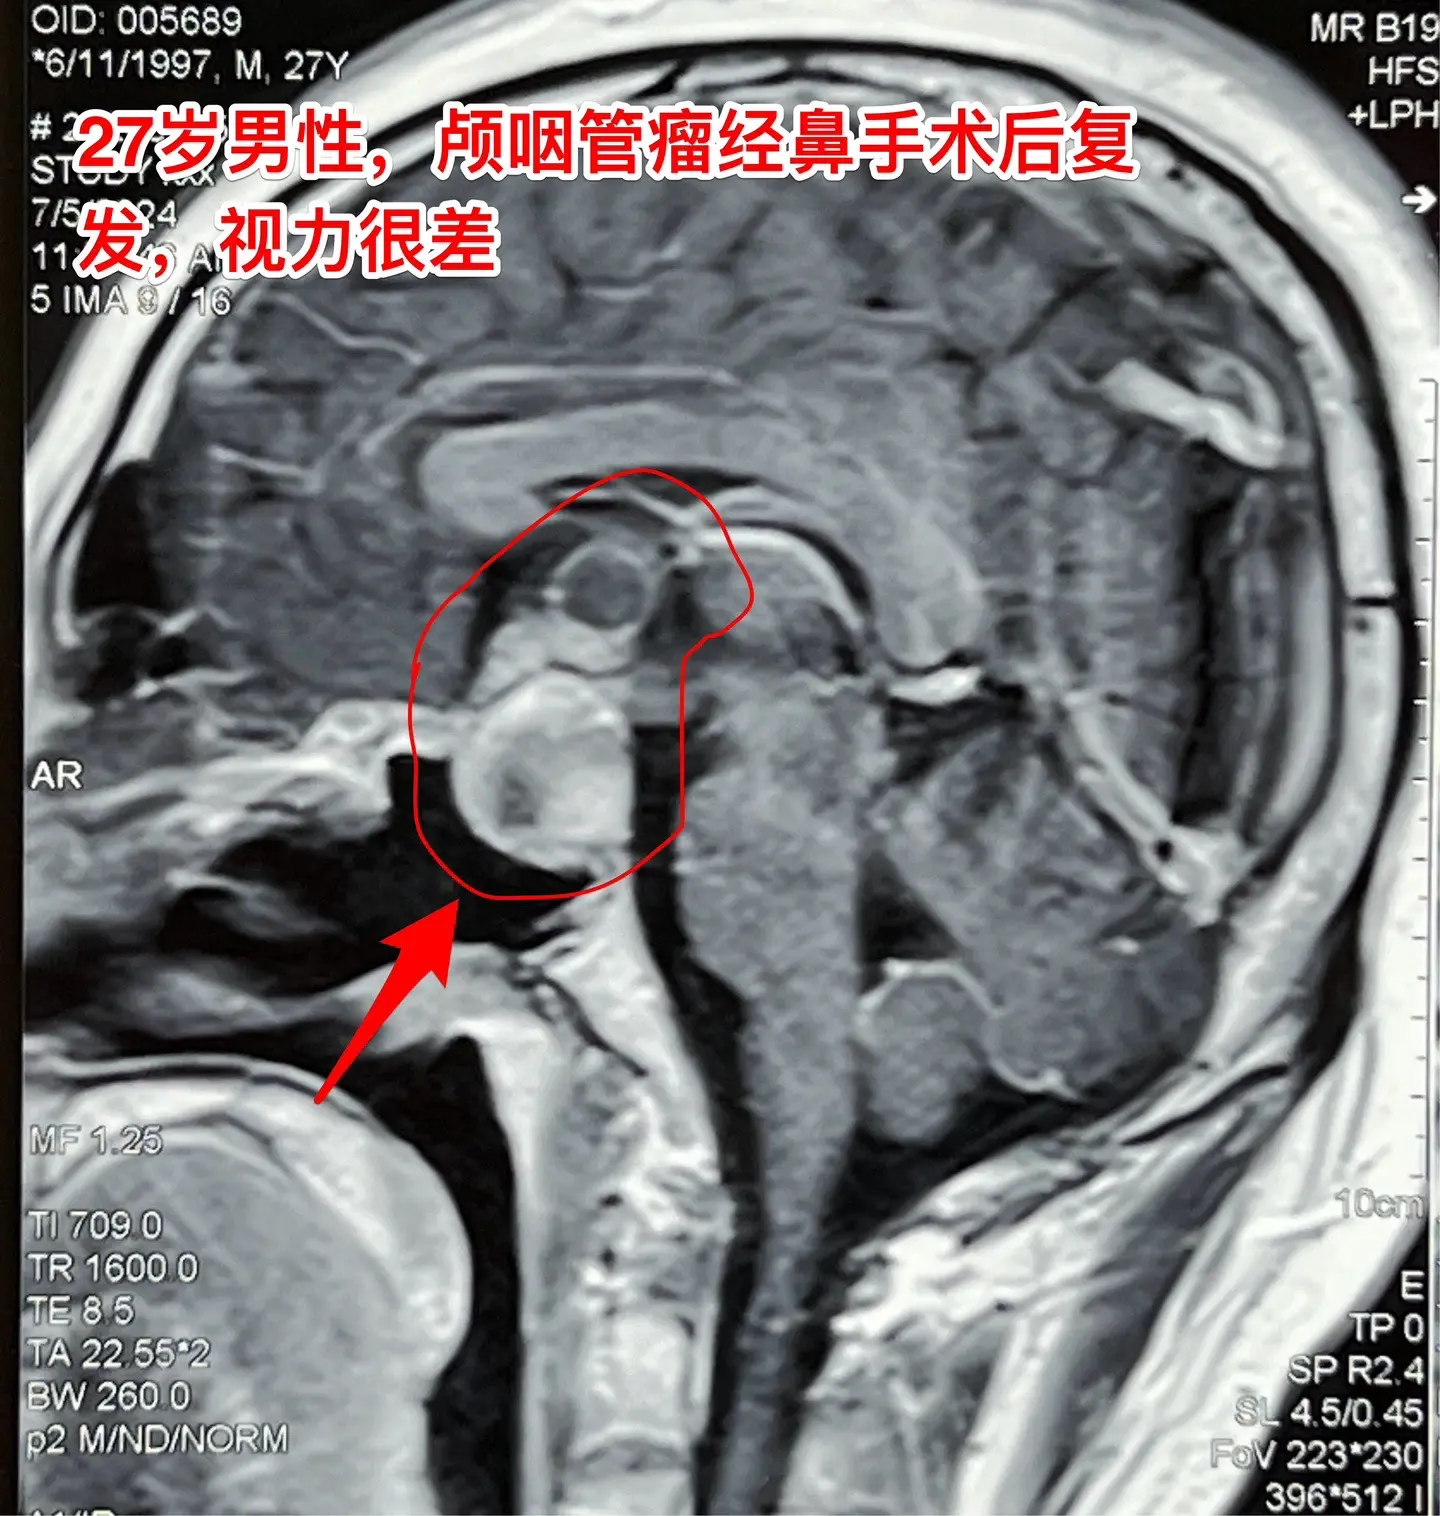

颅咽管瘤经鼻手术后8个月复发视力严重受损。27岁的甘肃小伙子因视力下降在外院诊断为颅咽管瘤,2023.11在兰州市某医院作了经鼻手术切除颅咽管瘤,肿瘤没有得到完全切除,视力稍有改善,出院后不久视力又呈下降趋势。2024年7月5日磁共振显示肿瘤体积很大。

头CT显示肿瘤密度稍高,没有钙化,见图5。患者视力很差,根本看不见视力表的第一行。看手机时手机几乎是贴着眼睛才能看见。

7月26日为他作了手术,手术过程中发现肿瘤为乳头型颅咽管瘤,与周围的脑组织粘连紧密,耗时十余小时才将肿瘤完全切除。